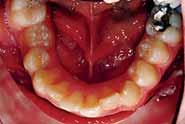

After 2 weeks of implant placement the patient came back. A preparation was done to the premolars at both sides and the impression was taken.

4 units bridge was fabricated for each side splinting the implant abutment to the 2 natural teeth of each side.

(DentoTemp of ITENA) long term temporary cement which is used as a Permanent cementation of implant-retained crowns.